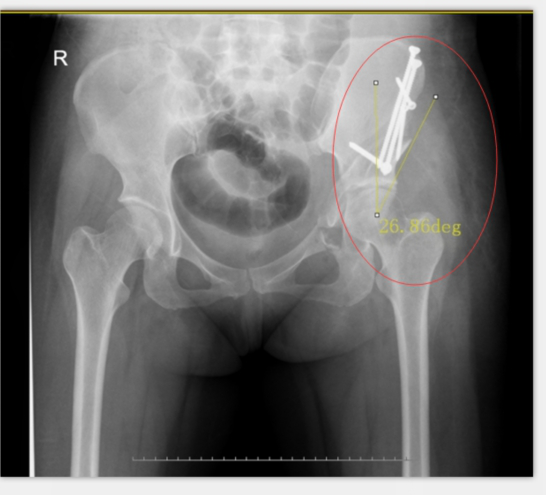

術(shù)后X光:CE角約26度,髖臼尺度正常